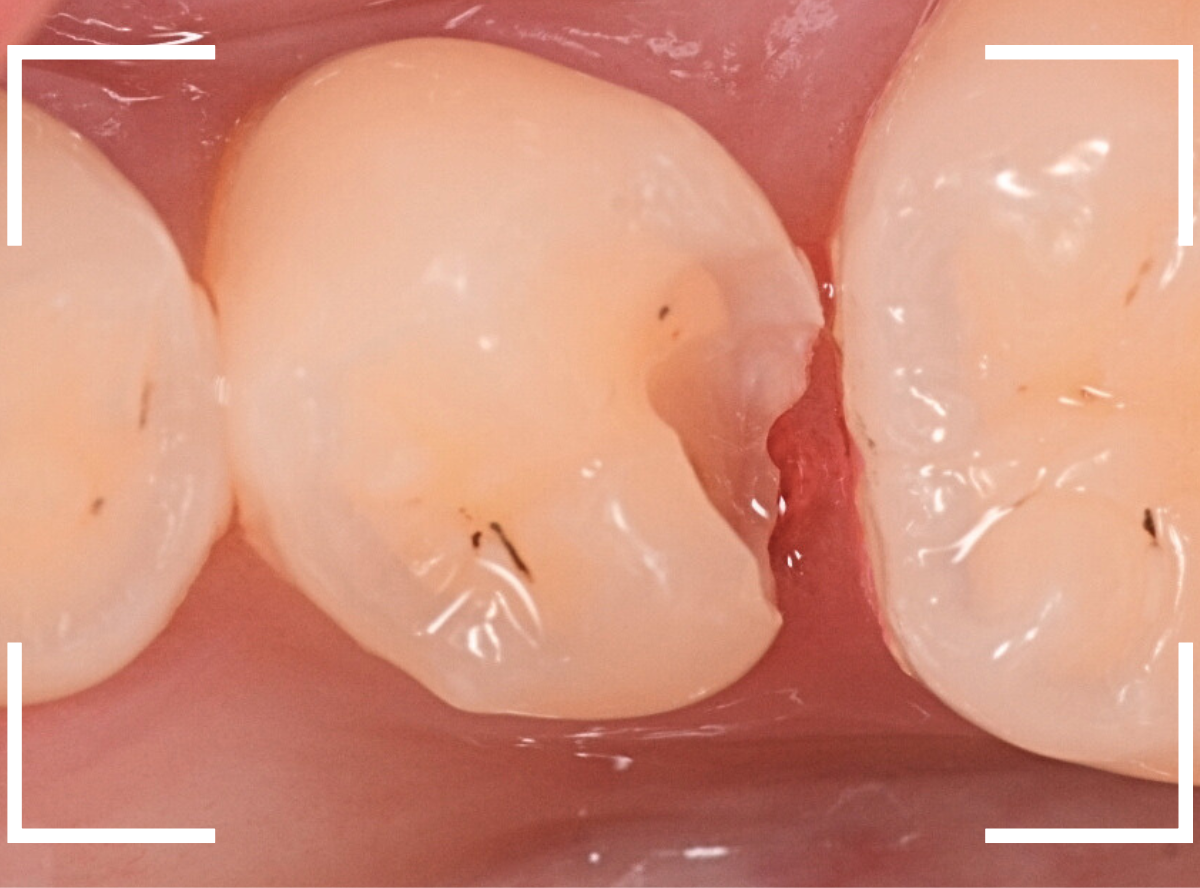

虫歯の治療を開始します。

隣の歯とのすき間を中心に広い虫歯になっていました。

虫歯治療後、特に症状もなく経過観察できましたので、つめものを作る治療に入ります。

セラミック治療をご希望されましたので、

小臼歯をE-MAX・インレー、

大臼歯をジルコニア・インレーで処置することになりました。